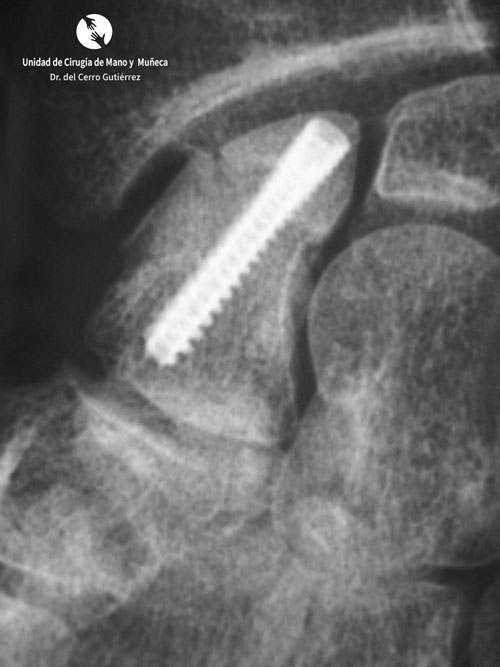

• Osteosíntesis abierta de las fracturas del escafoides: se puede realizar mediante abordaje volar o dorsal. El abordaje volar permite la visualización completa del escafoides. La síntesis de la fractura se realiza mediante un tornillo canulado.

Fractura del Escafoides Tornillo con Injerto